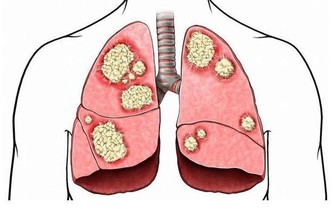

原來這名男子小時候曾罹患腦水腫 (hydrocephalus,俗稱腦積水),

但其實腦積水的問題未獲得根治,

在往後將近30年的時間,積水一點一滴佔據男子的腦部,

並將大腦的物質逐漸分解,導致最後只剩下10%的大腦。